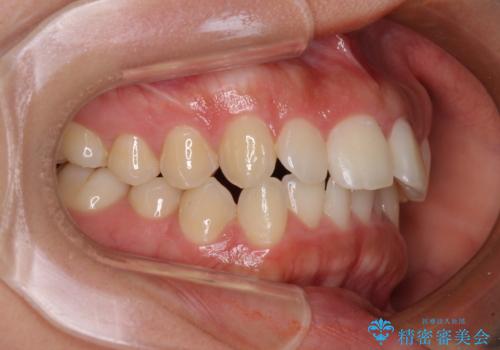

飛び出した上顎前歯 インビザラインで引っ込める

- 前歯の突出感を気にして来院された患者様です。

奥歯の咬み合わせは理想的な咬合に近く、インビザラインでも十分に対応できる歯列でした。

舌の突出癖を改善するためのトレーニングを行いつつ、上下歯列全体を後方に移動させ、更にはIPR(歯と歯の間を削る)によりスペースを獲得することで、口元の突出感を改善することとしました。